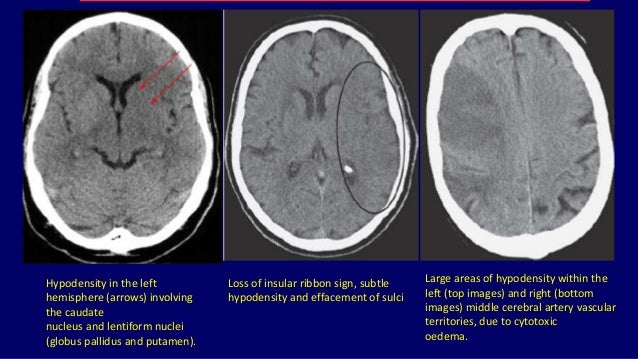

Ct Basics

www.slideshare.net nucleus lentiform thalamus caudate